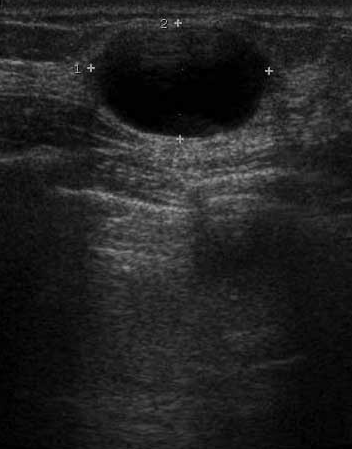

The target dataset was developed from 35 breast ultrasound scans that were segmented by an image-processing expert with extensive experience in breast lesion segmentation (the second author). The images, collected from the Web, are of different dimensions, ranging from to pixels (Figure 3, images resized for sake of illustration). These are the same images used to introduce EFIS originally [1].

Ultrasound images are generally difficult to segment, primarily due to the presence of speckle noise and low level of local contrast. It should be noted that the segmentation of ultrasound actually does require a complete processing chain, (including proper preprocessing and post-processing steps). However, the purpose of using these images was solely to demonstrate that the accuracy of the segmentation can be increased with the application of SC-EFIS.